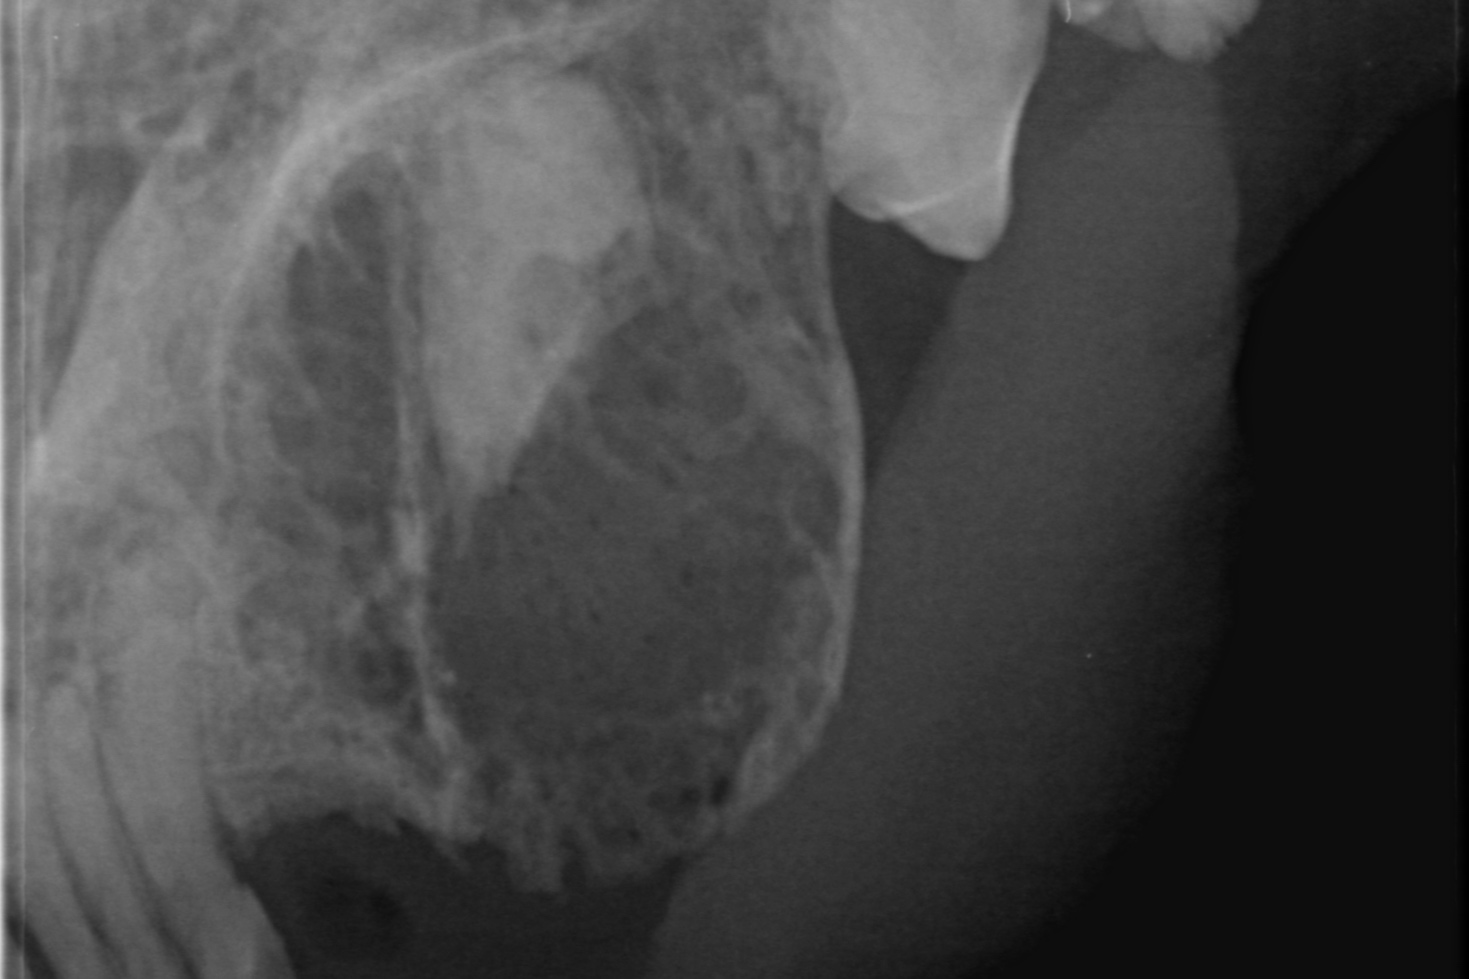

Auf diesen Bildern sehe ich etwas mehr als auf den herkömmlichen chemisch entwickelten Aufnahmen. Die Aufnahmen können vergrößert oder gefiltert werden. Sie lassen sich unkompliziert speichern und verschicken. Der Kunde kann eine Datei mitnehmen; der fachliche Austausch unter Tierärzten wird schneller.

Aber der Clou ist: Die Speicherfolien sind so klein, daß ich damit einen entscheidenden technologischen Vorteil gegenüber meiner alten Technik habe. Ich kann überlagerungsfrei jeden Zahn einzeln darstellen. Ich kann auch Pfötchen und Flügel röntgen, ohne gleich den ganz großen Apparatismus anzuwerfen.

Ein paar Beispielaufnahmen

aus unserer Röntgenpraxis